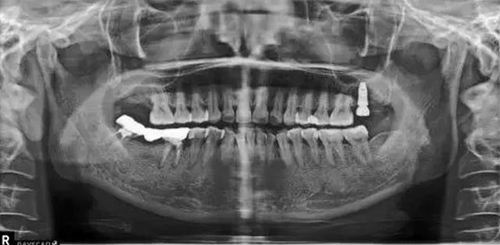

X片上可見(jiàn)T女士左上后牙缺失。根據(jù)患者口內(nèi)和全身狀況。制定計(jì)劃為:右上后牙種植修復(fù)。

種植術(shù)后三個(gè)月復(fù)查X片。可見(jiàn)左上種植體已植入?;謴?fù)良好。開(kāi)始著手進(jìn)行修復(fù)進(jìn)行二期手術(shù)。